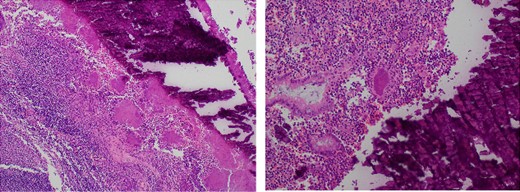

He underwent an emergency laparoscopic stapled caecectomy. Intraoperatively, the appendix was firmly adherent to the terminal ileum and right pelvic side wall, forming a dense fibrotic mass. This was bluntly dissected and given the appearance of an oedematous appendiceal base, the decision was made for a stapled caecectomy. Postoperatively, the patient recovered well and was discharged 3 days later. Interestingly, the histopathology of the specimen was reported as acute appendicitis with acute on chronic inflammation in the appendiceal mucosa and a luminal faecolith surrounded by actinomyces-like organisms (Fig. 2). There was no mention of sulfur granules on the pathology report. Advice was sought from the infectious diseases specialists and the patient was placed on a course of oral penicillins. The patient has ongoing follow up to ensure no recurrence of disease.

Microscopy slides demonstrating a luminal faecolith surrounded by Actinomyces.